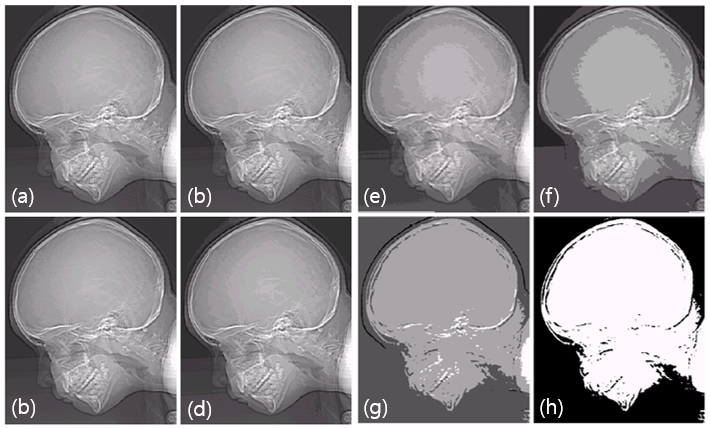

(a) 원본 : 456x374 해상도, 256 Gray Levels

(b) 128 Gray Levels

(c) 64 Gray Levels

(d) 32 Gray Levels

(e) 16 Gray Levels

(f) 8 Gray Levels

(g) 4 Gray Levels

(e) 2 Gray Levels